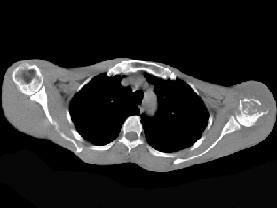

问题 患者,男,29岁,行走时不慎跌倒,曾拟为左肱骨头骨折并行固定,但半年后疼痛未减轻,触压局部骨质松软,如触及乒乓球感,明显叩击痛,请结合所提供图像,选择最佳答案 ( )

选项 A、骨转移瘤 B、骨结核 C、骨网状细胞肉瘤 D、左肱骨头骨折 E、化脓性骨髓炎

答案 C